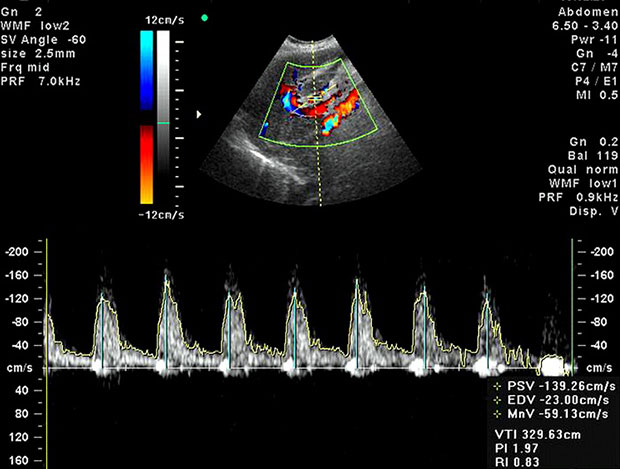

Принцип проведения допплерометрии практически не отличается от принципа проведения обычного УЗИ. В обоих случаях используются датчики с излучением. Правда, в первом его мощность все-таки сильнее, благодаря чему и удается оценить кровоток в маточных артериях, в сосудах плода и плаценты, а также их проходимость и просвет. На основании полученных данных впоследствии врачи смогут судить о развитии крохи и делать прогнозы относительно возможных осложнений беременности.

Стоит отметить, что она проводится на современных модулях аппаратов ультразвукового исследования. При этом специалист получается целый ряд данных, анализируя которые он и может оценить кровоснабжение.

Нормы допплерометрии выглядят следующим образом: